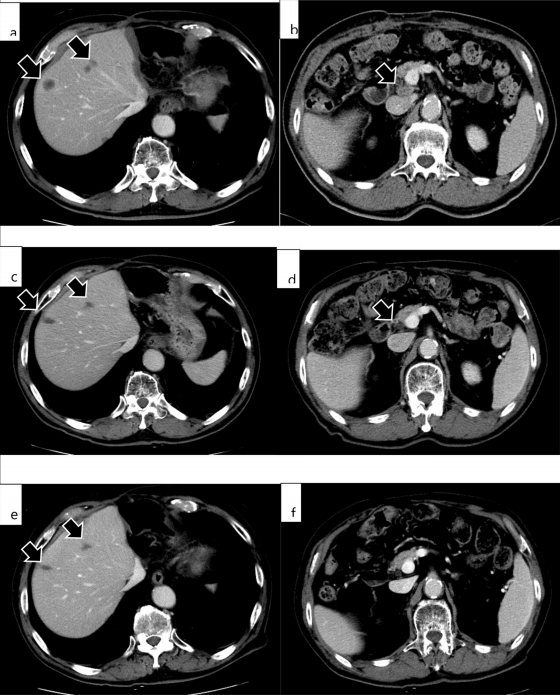

《J CLIN GASTROENTEROL》期刊的病例报告显示,一名肝内胆管癌伴肝、淋巴结转移患者接受帕博利珠单抗治疗,用药四次后,CA19-9 降至正常,CT 显示转移性肝肿瘤及增大的肝门淋巴结明显缩小。但 14 次用药后,患者出现躯干、四肢瘙痒及皮疹,被诊断为大疱性类天疱疮,遂停药并接受对症治疗。

令人意外的是,停药 9 个月后,患者仍存活且无肿瘤复发,证明即便停用帕博利珠单抗,疗效仍能持续。

腹部MRI显示第二次手术后4个月肿瘤复发;停止派姆单抗治疗9个月后复发病变未见变化(e,f)